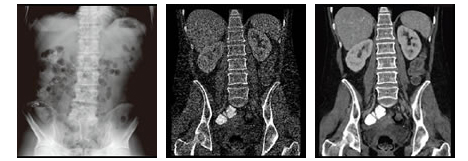

同一被ばく量(0.7ミリシーベルト)で撮影した腹部画像

左:一般X線装置 中央:Veo非搭載CT 右:Veo搭載CT